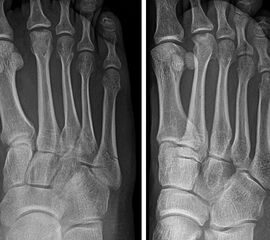

Lawrence und Botte Zone II

Abbildung 4

Kontrovers diskutiert wird die Behandlung der Frakturen in Zone II nach Lawrence und Botte (Abb. 4). Wie einleitend beschrieben, scheint hier unter anderem die inkonsistente Terminologie ursächlich zu sein. Das Synonym „Jones’ Fraktur“ oder „True Jones’ Fraktur“ wurde sowohl für Lawrence und Botte Zone II, als auch für Zone III Frakturen verwendet 1986. Entsprechend ist die Interpretation dieser Studien nur eingeschränkt möglich. 2013 publizierten Roche und Calder 20 eine systematische Literaturarbeit, in welcher sie die Ergebnisse verschiedener Behandlungsstrategien für „Jones Frakturen“ analysierten. 26 Studien mit 630 Frakturen (Level of Evidence I-IV) wurden eingeschlossen. 358 der Frakturen wurden operativ behandelt. Die knöcherne Konsolidierungsrate für operativ versorgte Frakturen betrug 96%, die für konservativ behandelte Frakturen 76%. Allerdings erfolgte keine Differenzierung zwischen Lawrence und Botte Zone II und Zone III Frakturen. Spezifischere Ergebnisse lieferte eine weitere systematische Literaturarbeit 7. In dieser wurden nur prospektive Studien eingeschlossen, in welchen die Frakturen nach Lawrence und Botte klassifiziert wurden bzw. klassifiziert werden konnten. Die Autoren kamen zu dem Ergebnis, dass die frühfunktionelle Behandlung von Lawrence und Botte Zone I und Zone II zu guten bis sehr guten Ergebnissen führt.